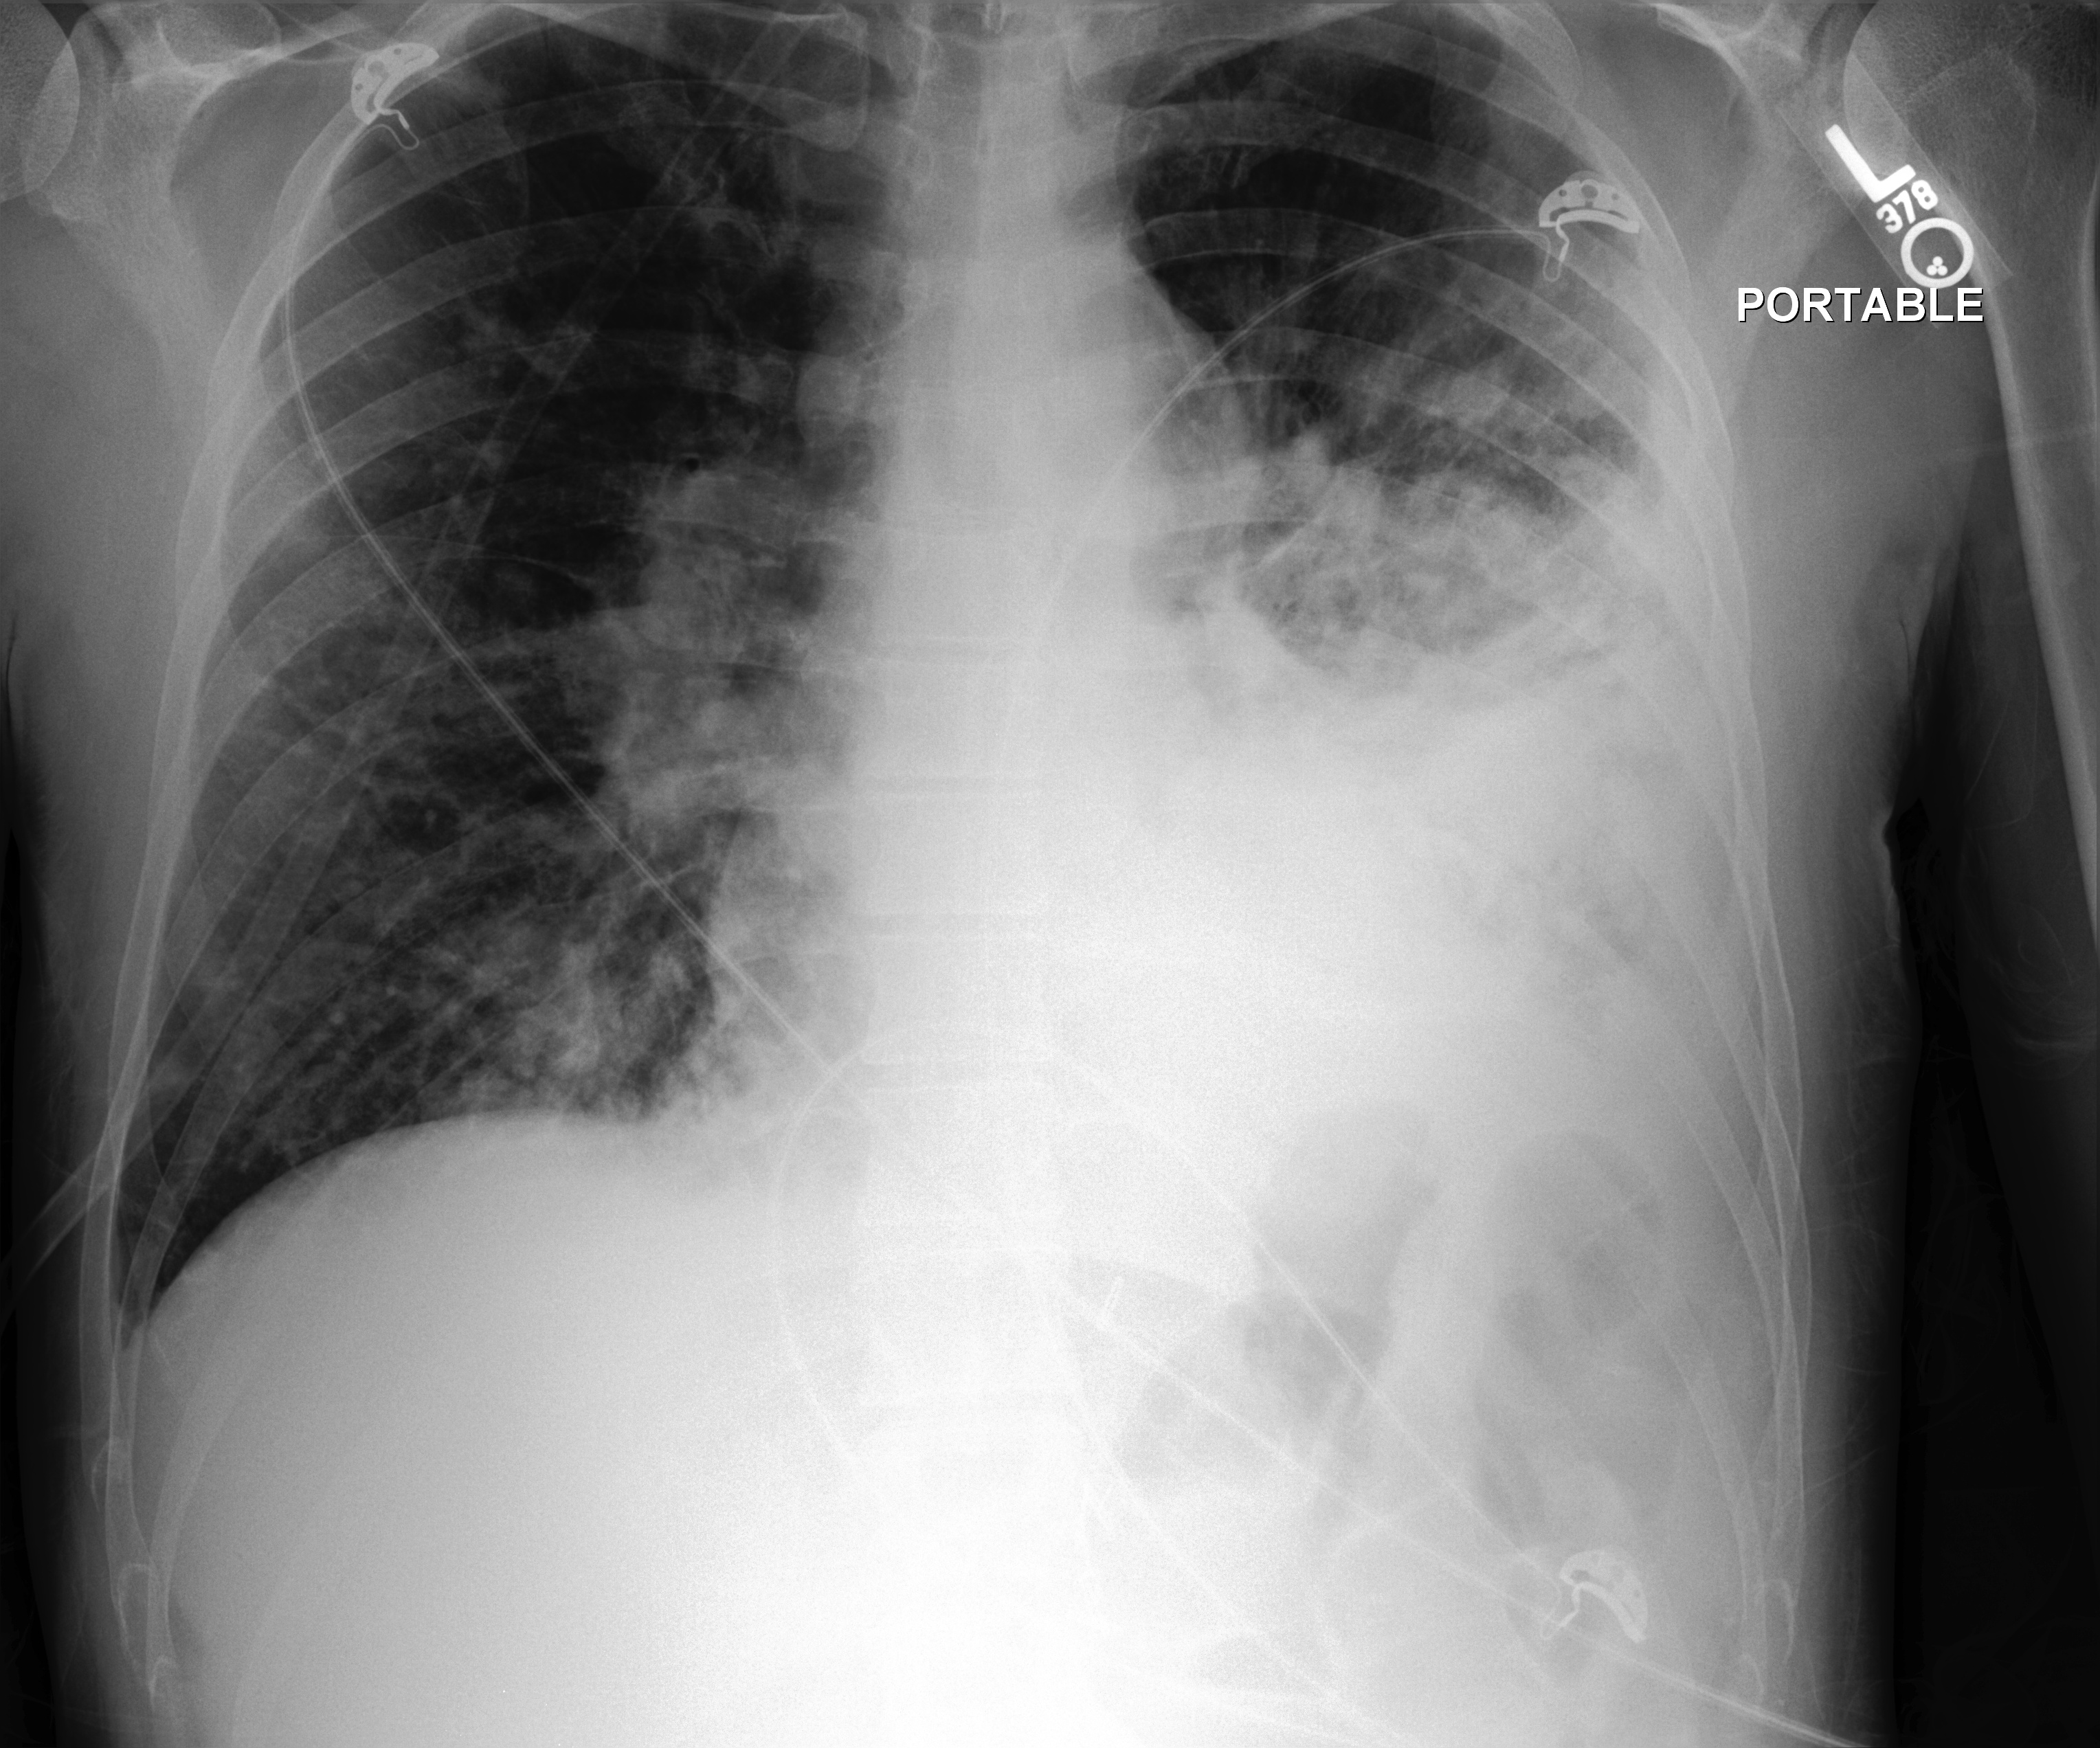

Example 2

[Uncaptioned image]

Generated

レントゲン写真を読影した結果、心臓の左室が大きく、右室が小さいことがわかりました。肺野は均一に空気を含み、骨は正常です。心臓の左室の異常は心不全の可能性を示唆しています。

(The X-ray examination revealed that the left ventricle of the heart is enlarged, while the right ventricle is small. The lung fields are uniformly aerated, and the bones are normal. The abnormality in the left ventricle suggests the possibility of heart failure.)

Ground truth

胸骨正中切開のワイヤーと縦郭のクリップが見られる。肺野は清明で、浸潤影や胸水、気胸はない。心臓や縦郭陰影は正常。骨病変はない。右横隔膜下にフリーエアはない。

(Wires from a median sternotomy and clips in the mediastinum are visible. The lung fields are clear, with no infiltrates, pleural effusion, or pneumothorax. The cardiac and mediastinal silhouettes are normal. There are no bone lesions. No free air is seen under the right diaphragm.)